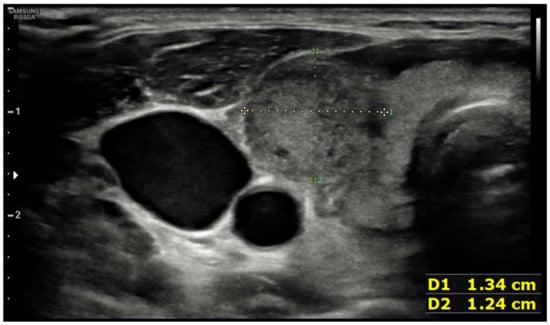

| Ultrasound findings at presentation | Asymmetric thyroid enlargement with two hypoechoic areas with no internal vascularity on right thyroid lobe | Diffuse thyroid enlargement with hypoechoic areas with heterogeneous echotexture and no evidence of increased vascularity | Diffuse enlargement of thyroid gland with hypoechoic nodules with hyperechoic shoots (micronodular pattern) without increase in vascularity | ||||||||||||||

| Ultrasonographic findings | ||||

| Hypoechoic areas | 8 (80%) | 3 (75%) | 5 (83.3%) | 1 |

| Heterogeneous echotexture | 4 (40%) | 1 (25%) | 3 (50%) | 0.571 |

| Reduced blood flow at Doppler-US | 6 (60%) | 1 (25%) | 5 (83.3%) | 0.119 |